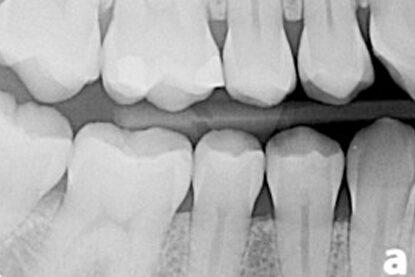

ادخل إلى عالم تشخيص الأسنان المتقدم في عيادة ليفانتين لطب الأسنان في دبي. توفر تقنية الأشعة السينية الحديثة الخاصة بنا رؤية واضحة ومفصلة وشاملة لصحة فمك. يتم إجراء الأشعة السينية للأسنان من قبل أطباء الأسنان الخبراء ، وهي طريقك للحصول على ابتسامة أكثر صحة.

إذا كنت تعاني من مشاكل الأسنان ، فإن الأشعة السينية للأسنان هي إجراء موصى به لتضمينه في خطة علاج الأسنان الخاصة بك. يوفر رؤية دقيقة لأسنانك ويمكن أن يساعد في تحديد أي مشاكل والتخلص منها بسرعة. في حين أنه قد يكون من الصعب التعامل مع مشاكل الأسنان على الفور ، فإن الطبيعة التفصيلية للأشعة السينية للأسنان تسمح لأخصائيي الأسنان بتحديد المشكلات بدقة كاملة وتقديم العلاج المناسب. من خلال اختيار الأشعة السينية للأسنان ، يمكنك التأكد من أنه سيتم تحديد أي تحديات محتملة ومعالجتها على الفور ، مما يسمح لك بالتركيز على الخطوات اللازمة للحفاظ على صحة فمك.

تحديد التسوس

الأشعة السينية للأسنان قادرة على تحديد التجاويف وتقييم حالتها الحالية. بالإضافة إلى ذلك ، يمكن أن يوفر رؤية لجذور الأسنان ، وهو أمر حاسم في تحديد ما إذا كانت العناية الإضافية ضرورية.

صحة منطقة العظام

يمكن للأشعة السينية للأسنان أيضًا التحقق من صحة العظام المحيطة بالسن وتحديد ما إذا كانت أمراض اللثة عاملاً مساهماً. علاوة على ذلك ، يمكن أن يساعدك على فهم أسباب نمو الأسنان ، والتي يمكن أن تكون مفيدة لصحة فمك على المدى الطويل.

يمكن لفحص الأسنان الجسدي أن يعطي طبيب أسنانك نظرة محدودة فقط على صحة فمك. تُستخدم الأشعة السينية جنبًا إلى جنب مع الفحص البدني وتعمل كأداة تشخيصية مهمة.

إنها توفر لطبيب أسنانك القدرة على الرؤية بين أسنانك وتحت خط اللثة وجذور أسنانك.